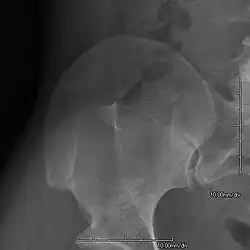

An elbow of a man with nail–patella syndrome (NPS)

-

This is a view from a different angle of the same man's other elbow